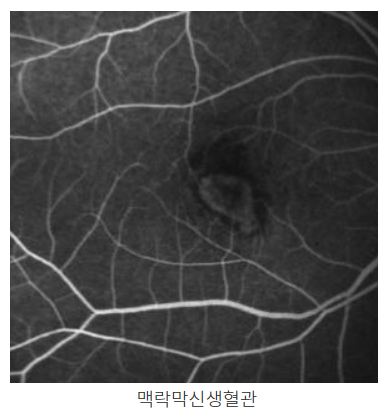

- OCT (광학 단층 촬영): 중심성 장액성 망막병증은 OCT를 통해 망막의 두께와 액체 축적을 확인할 수 있습니다. 이를 통해 질환의 진단과 진행 상황을 모니터링할 수 있습니다.

- 형광안저촬영 (FA): 형광안저촬영을 통해 혈관 누출이 발생하는 지점을 확인할 수 있으며, 질환의 경과와 치료의 효과를 평가하는 데 유용합니다.

- 형광안저촬영(Fundus Fluorescein Angiography): 망막의 혈관 상태를 확인하고, 액체 누출 부위를 감지하는 데 사용됩니다.